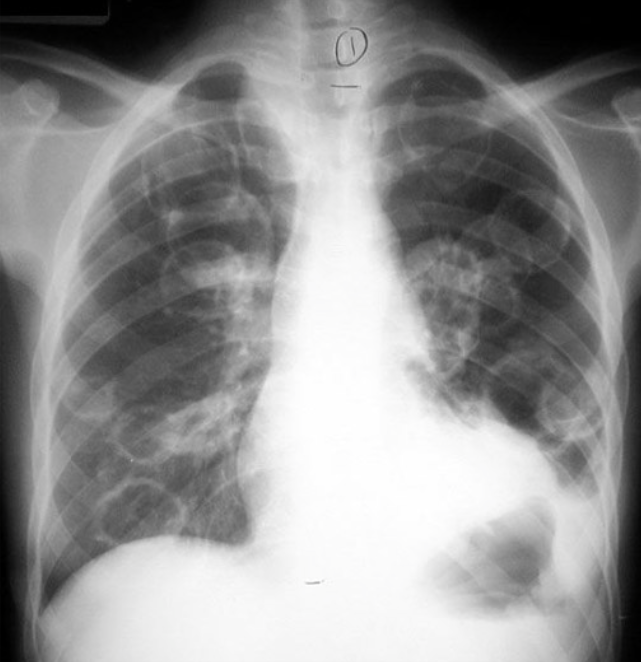

What is shown in the image?

Multiple Cavities